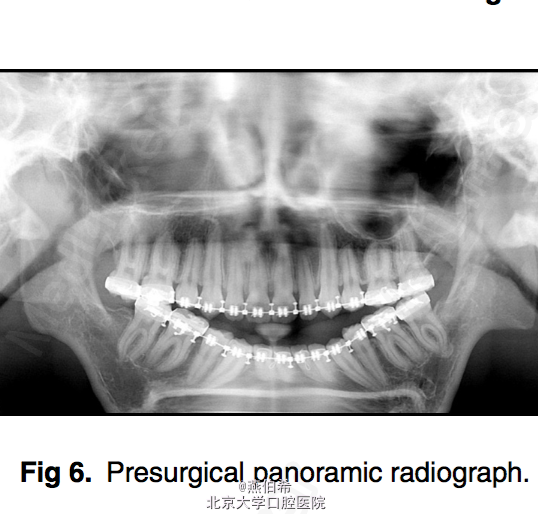

Treacher Collins综合征 扩弓解决宽度不调,拔4个4矫正牙量骨量不调, 后行口外反L行截骨术矫正颌骨问题

术后效果良好。 Treacher Collins 综合征,下颌-面骨发育不全 患病率为每50,000活婴儿中有1个 其表现为颧弓发育不全(81%),小颌畸形(78%)以及由于外耳道闭锁引起的外耳形态异常,同时可能听小骨确实引起的传导性耳聋。 口腔内的表现为高腭穹窿,唇裂,腭裂,牙釉质发育不良,及骨骼导致的前牙开牙合。前磨牙不萌出和上磨牙异位萌出也很常见。 (AJODO,November 2014 Vol 146 Issue 5)